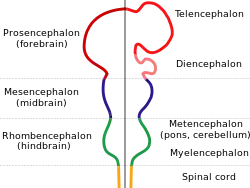

| Diagram depicting the main subdivisions of the embryonic vertebrate brain. | |

Holoprosencephaly (HPE) is a cephalic disorder in which the prosencephalon (the forebrain of the embryo) fails to develop into two hemispheres, typically occurring between the 18th and 28th day of gestation.[1] Normally, the forebrain is formed and the face begins to develop in the fifth and sixth weeks of human pregnancy. The condition also occurs in other species.

When the embryo's forebrain does not divide to form bilateral cerebral hemispheres (the left and right halves of the brain), it causes defects in the development of the face and in brain structure and function.